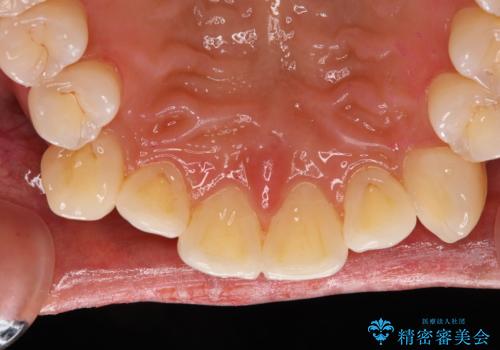

前歯が痛い!|歯の色が気になる!|精密根管治療後、オールセラミッククラウンで審美修復